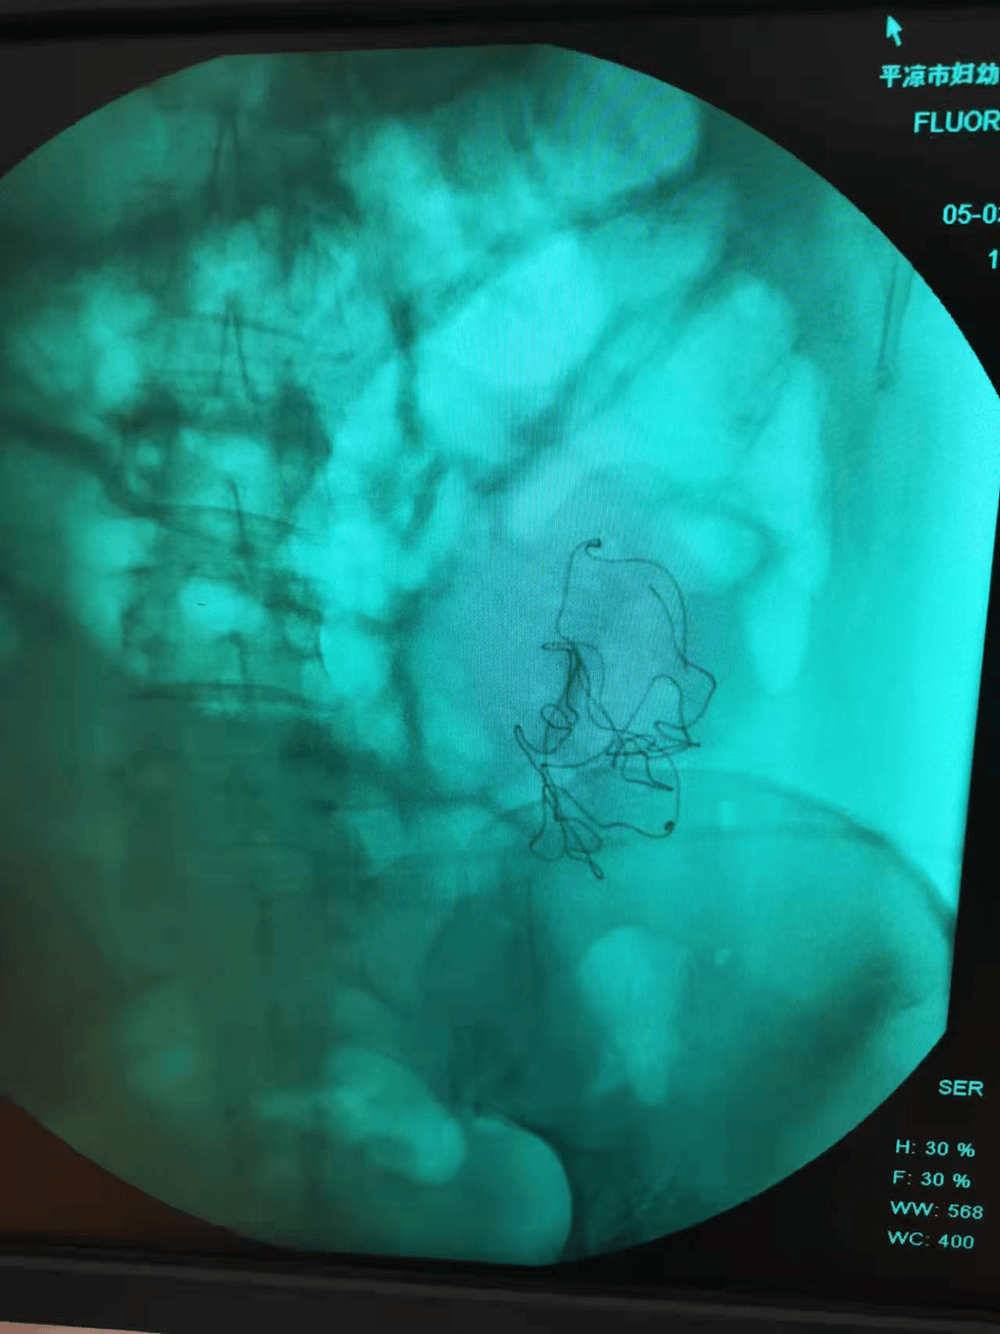

在秦红利多次请求下,院方终于将当时的检查影像交给了她。影像中,腹腔内异物影清晰可见。然而,在当天的手术记录中,这一异常没有留下任何痕迹。

秦红利分娩后,进行X光检查发现异物清晰可见。本文图片均为 受访者供图

手术记录中,二次开腹的原因是腹腔渗血,并写道:“因病情紧急在产房行急诊剖宫产术,为确保病人安全急行X线透视以观察腹腔内情况,X线透视显示有少量液平面,考虑血管收缩渗血可能,遂入手术室在静脉麻下行腹腔探查,发现腹膜一小血管渗血立即缝扎止血,再次探查腹腔无异常遂常规关腹”。

对于“能否准确判断手术中遗留的纱布样异物是位于患者体内还是体外?”,法大法庭科学技术鉴定所答复称,被告(医院方)提供的材料显示为纱布位于患者身下的转运垫之间,事实如何鉴定机构无法查证,但由此导致秦红利二次开腹,应由被告医方承担相应责任。